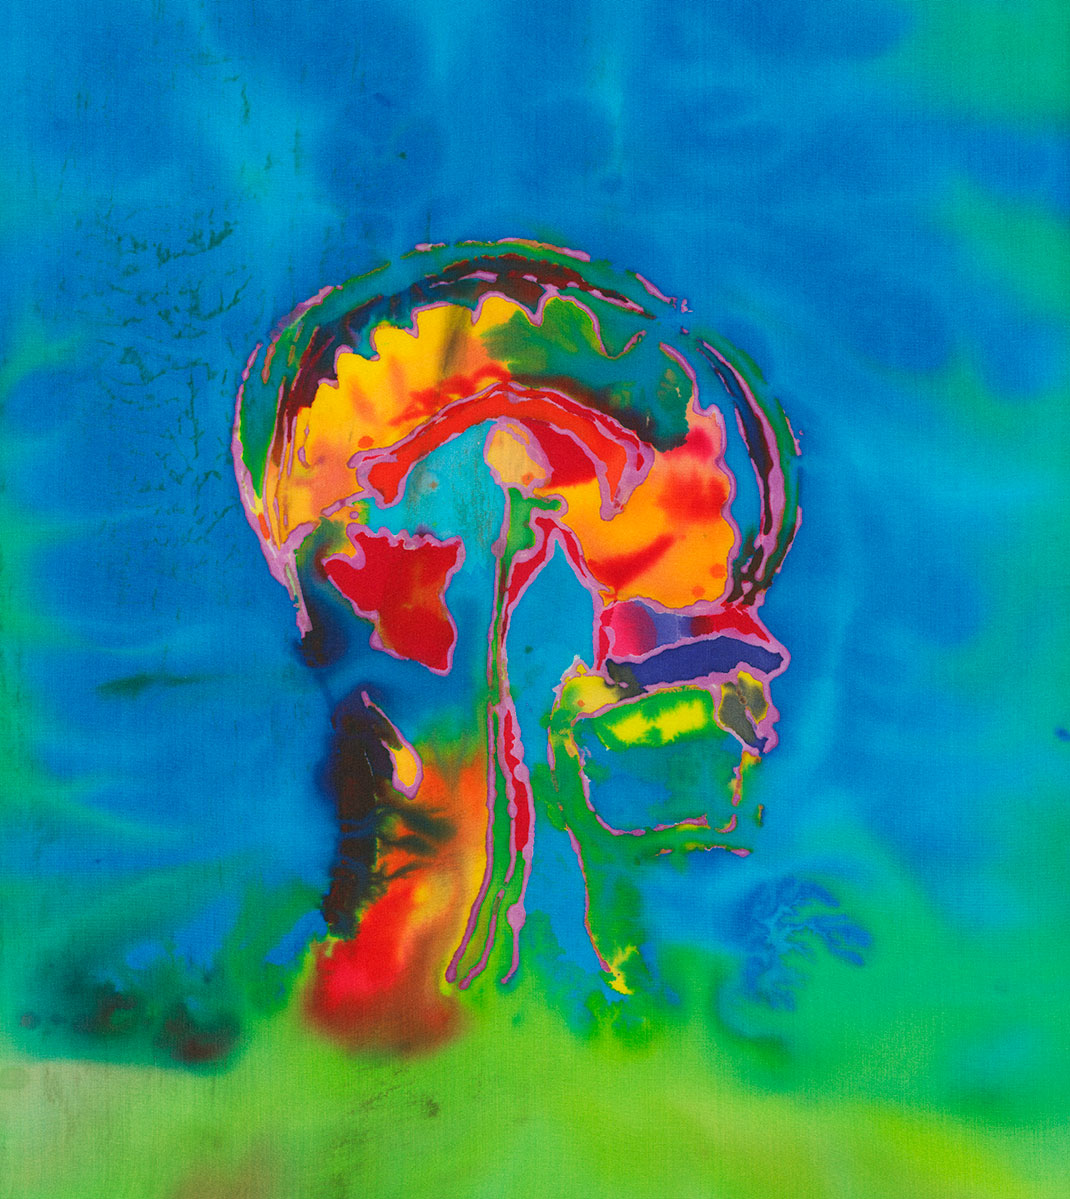

Elle trouve alors sa source d’inspiration dans sa maladie à travers ses IRMs. « Mes nombreux traitements m’ont donné envie de réinterpréter l’imagerie médicale. Les patients, souvent anxieux, ne voient que laideur et effroi dans les pixels noirs et gris des IRMs. J’ai alors ressenti le besoin vital de les utiliser pour montrer les merveilles et la beauté de nos cerveaux, y compris ceux souffrant d’une maladie. Je veux guérir les patients de la peur de regarder leurs IRMs », s’émeut Elizabeth.

En réutilisant ses scanners, Elizabeth Jameson cherche à insuffler des émotions et des sentiments dans la froideur technologique. Pour cela, elle utilise de nombreux supports : la peinture sur soie ou encore des impressions à partir de gravures sur cuivre ou sur plaque solaire. Ensuite, elle renforce la couleur de ses images grâce à de la peinture, des crayons ou du pastel sec. Le résultat offre une collection brillante, colorée, pleine d’émotion et de symbole.

Maintenant tétraplégique, Elizabeth crée avec l’aide d’un assistant. Selon elle, ses impressions ne sont pas qu’un moyen de faire la chronique des changements de son cerveau, qu’elle qualifie d’« organe le plus sacré ». Son travail est également un moyen de devenir plus familière avec ces changements, pour les rendre moins terrifiants. « Mon art est composé à 90 % de mon cerveau, tout simplement parce que je suis mon cerveau », conclut-elle.